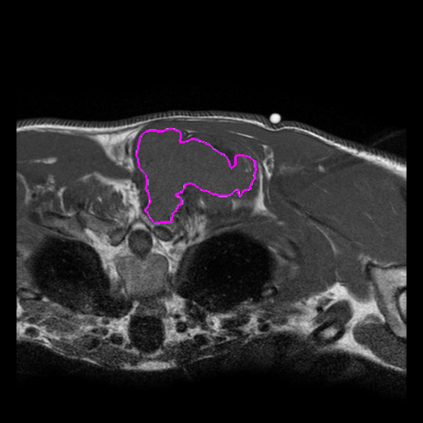

Radiomics uses quantitative medical imaging features to predict clinical outcomes. Currently, in a new clinical application, finding the optimal radiomics method out of the wide range of available options has to be done manually through a heuristic trial-and-error process. In this study we propose a framework for automatically optimizing the construction of radiomics workflows per application. To this end, we formulate radiomics as a modular workflow and include a large collection of common algorithms for each component. To optimize the workflow per application, we employ automated machine learning using a random search and ensembling. We evaluate our method in twelve different clinical applications, resulting in the following area under the curves: 1) liposarcoma (0.83); 2) desmoid-type fibromatosis (0.82); 3) primary liver tumors (0.80); 4) gastrointestinal stromal tumors (0.77); 5) colorectal liver metastases (0.61); 6) melanoma metastases (0.45); 7) hepatocellular carcinoma (0.75); 8) mesenteric fibrosis (0.80); 9) prostate cancer (0.72); 10) glioma (0.71); 11) Alzheimer's disease (0.87); and 12) head and neck cancer (0.84). We show that our framework has a competitive performance compared human experts, outperforms a radiomics baseline, and performs similar or superior to Bayesian optimization and more advanced ensemble approaches. Concluding, our method fully automatically optimizes the construction of radiomics workflows, thereby streamlining the search for radiomics biomarkers in new applications. To facilitate reproducibility and future research, we publicly release six datasets, the software implementation of our framework, and the code to reproduce this study.

翻译:放射科使用定量医学成像特征来预测临床结果。目前,在一个新的临床应用中,通过一个超常试验和高压过程,通过人工操作,从广泛的现有选项中找到最佳放射法。在本研究中,我们提议了一个框架,自动优化每个应用程序的放射工作流程的建设。为此,我们将放射作为模块工作流程,并包括每个部件的大量通用算法。为了优化每个应用程序的工作流程,我们使用随机搜索和聚合的自动机学习方法。我们用12种不同的临床应用来评估我们的方法,结果在曲线下应用的以下领域:1) 脂色瘤(0.83);2) 脱氧型纤维瘤(0.82);3 初级肝脏肿瘤(0.80);4 气肠肿瘤(0.77)、5 彩虹肝脏移植(0.61); 6 脑膜细胞变异常(0.45); 7) 肝细胞变异常(0.8) 脑纤维变异位(0.80); 9) 直径直线型癌症(0.74) 和头型癌症(0.77) 直径研究(10) 。